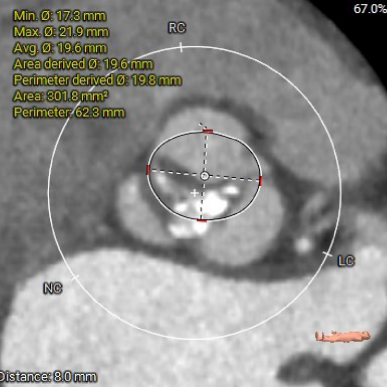

主动脉根部测量

瓣上结构测量

冠脉阻挡风险及钙化评估

1. Type 1 型二叶式主动脉瓣,瓣叶增厚伴中度钙化,L-N间钙化融合嵴,左室流出道呈敞口型;

2. 冠脉开口高度尚可,左右冠瓣叶冗长,切线位左右冠瓣叶长度>>冠脉开口到瓣叶根部附着缘距离;冠脉未见明显钙化斑块;

3. 三窦大小不一,瓦氏窦、窦管交界内径偏小,升主动脉轻度扩张;左室腔内径尚可,心室壁未见明显增厚;

4. 瓣环水平夹角51°,主动脉弓夹角偏锐利,弓距偏小;